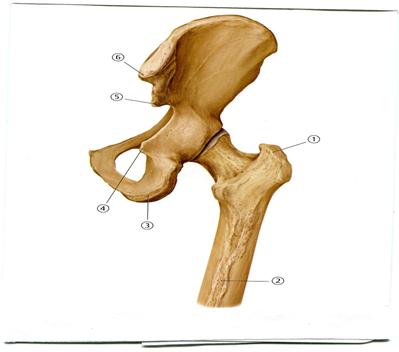

44. Төменде көрсетілген суреттегі белгіленген № 4 анатомиялық құрылымды атаңыз.

A. Алдыңғы жоғарғы қылқан

+B. Алдыңғы төменгі қылқан

D. Үлкен ұршық

E. Шонданай төмпегі